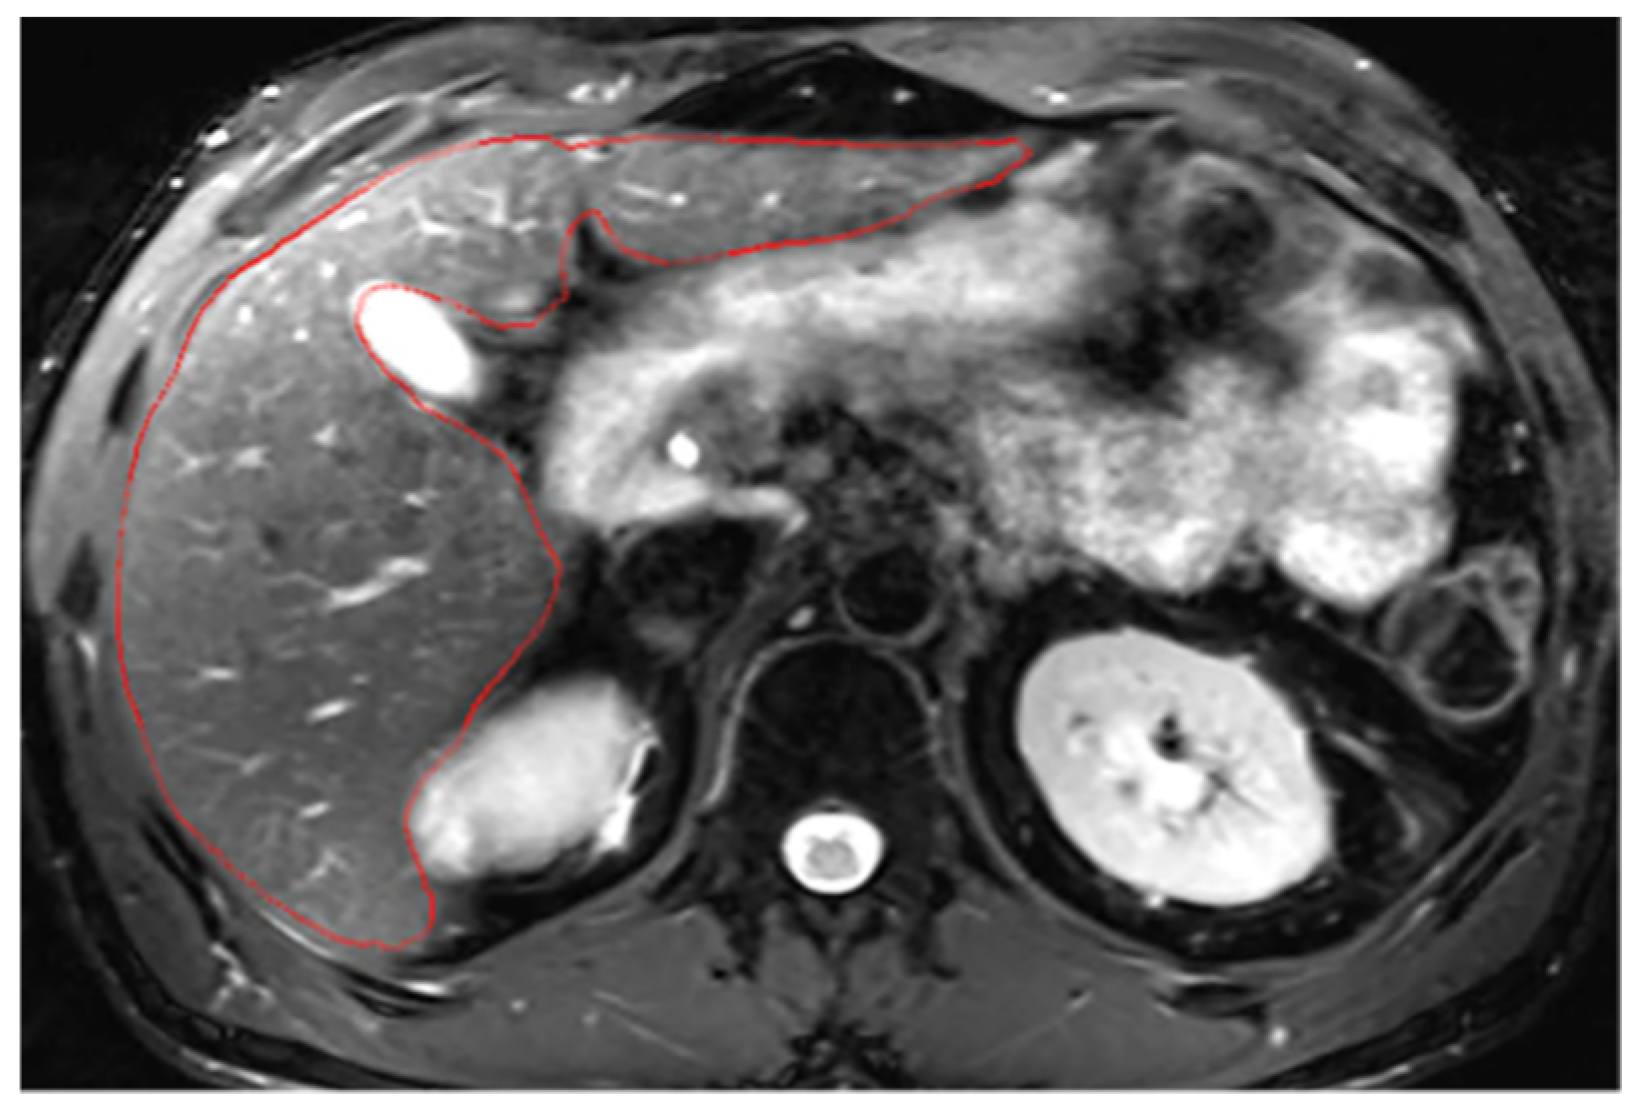

Appendix A.2. Hepatic Hilum Segmentation